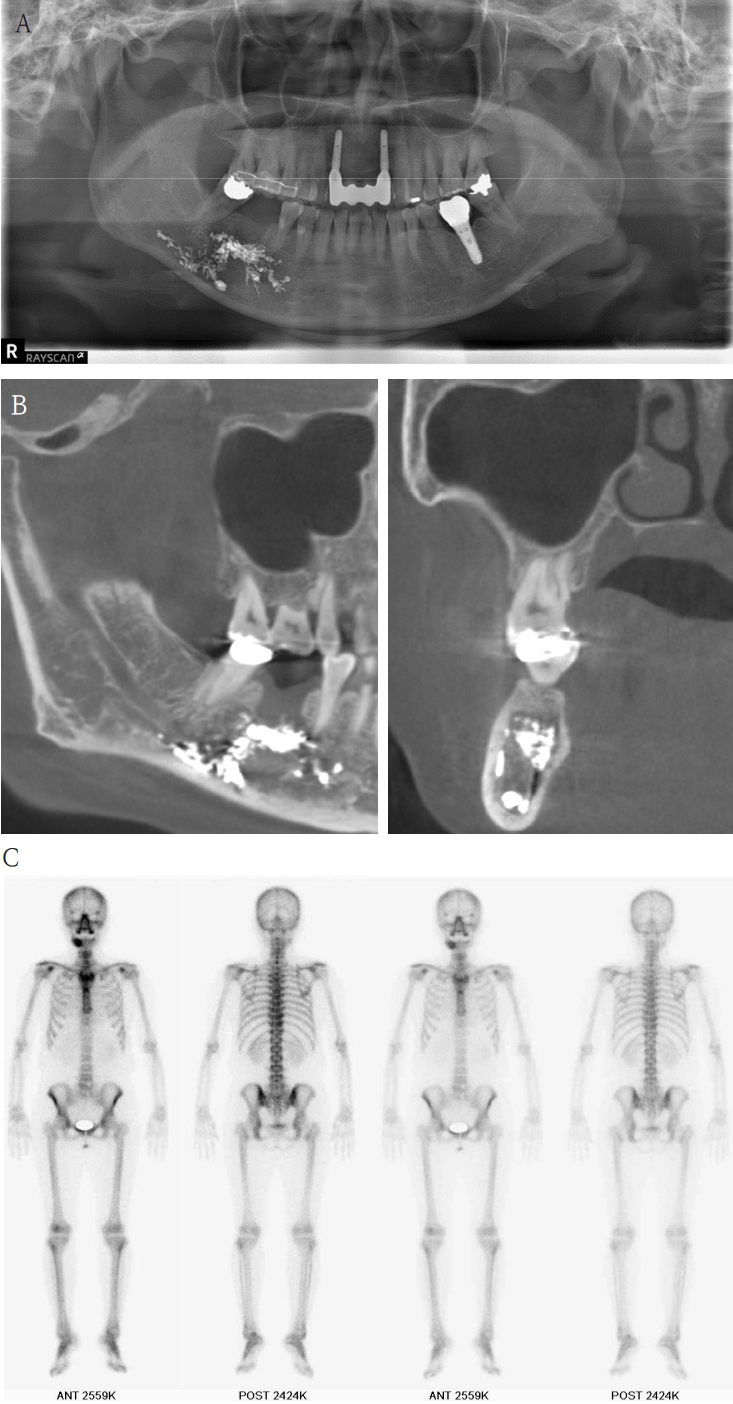

A 63-year-old female presented three days after endodontic treatment of the mandibular left second molar (#37) with symptoms of numbness in the left lower lip and gingiva. A panoramic radiograph and cone-beam computed tomography (CBCT) revealed extrusion of Calcipex II into the mandibular canal (Fig. 1). Initial neurosensory testing demonstrated mild hypoesthesia. She was admitted for foreign body removal and neurorrhaphy under general anesthesia. A post-operative panoramic radiograph confirmed the removal of the foreign body (Fig. 2). Although surgical curettage and neurorrhaphy were performed on the fourth day post-onset, no significant symptom relief was noted at the one- and two-week follow-ups. At the three-month follow-up, she reported persistent numbness with mild neuropathic discomfort but no marked improvement. A follow-up neurosensory exam is scheduled for the six-month check-up.

Figure 1.

A. Pre-op panoramic radiograph of Case 1 patient. B. Pre-op CBCT of Case 1 patient